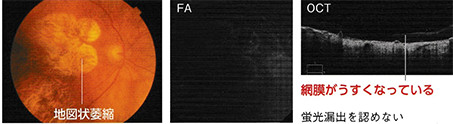

萎縮型

網膜色素上皮が、加齢により萎縮していくタイプです。このタイプは進行が緩やかで、視力の予後も比較的良好ですが、滲出型に移行することもあります。

※FA:フルオレセイン蛍光眼底造影 OCT:光干渉断層計